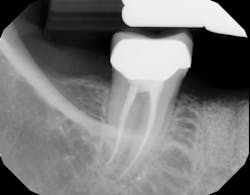

Related video: Extraction and socket grafting in preparation for dental implant placement

This surgical video demonstrates removal of a tooth with loss of buccal plate and grafting of the remaining socket with Geistlich Bio-Oss Collagen and Geistlich Bio-Gide to preserve the ridge for implant placement.